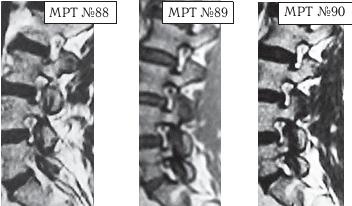

На МРТ № 88 наблюдается состояние до лечения методом мануальной терапии: дегенеративно-дистрофический процесс во всех межпозвонковых дисках поясничного отдела позвоночника, спондилёз, остеофитоз, спондилоартроз дугоотростчатых суставов в сегментах LIII-LIV, LIV-LV, LV-SI а также стеноз фораминальных отверстий в данных сегментах.

На МРТ № 89 наблюдается состояние того же пациента сразу после проведения лечебного сеанса мануальной терапии (в течение одного часа).

Во время проведения манипуляций мануальным терапевтом пациент слышал характерный «хруст» в дугоотростчатых суставах позвоночника. Мануальный терапевт пояснил, что данный «хруст» говорит о том, что соотношения суставных поверхностей в дугоотростчатых суставах восстановлены, сублюксация устранена. Пациент также отметил, что после сеанса мануальной терапии он почувствовал явное облегчение боли, лёгкость, подъём настроения.

Объективно положительных изменений при визуальном сравнении МРТ-снимков до и после проведения лечебного сеанса мануальной терапии не наблюдается. Стеноз фораминальных отверстий без изменений, соотношения суставных поверхностей дугоотростчатых суставов — без изменений.

Объективно отрицательные изменения при визуальном сравнении МРТ снимков до и после проведения лечебного сеанса мануальной терапии наблюдаются и проявляются кровоизлиянием в полость дугоотростчатых суставов в сегментах LIII-LIV, LIV-LV, LV-SI

На МРТ № 90 наблюдается состояние того же пациента после проведения трёх лечебных сеансов мануальной терапии с 24-часовым интервалом между сеансами.

Объективно положительных изменений при визуальном сравнении МРТ-снимков до и после проведения трёх лечебных сеансов мануальной терапии не наблюдается.

Объективно отрицательные изменения при визуальном сравнении МРТ-снимков до и после проведения трёх лечебных сеансов мануальной терапии наблюдаются и проявляются значительным кровоизлиянием в полость дугоотростчатых суставов в сегментах LIII-LIV, LIV-LV, LV-SI.

Вывод: исходя из объективного визуального наблюдения, согласно снимкам МРТ-обследования и их сравнения, можно сделать вывод, что применение мануальной терапии в данном конкретном случае положительных изменений не дало. Кровоизлияние в полости дугоотростчатых суставов поясничного отдела позвоночника после применения мануальной терапии можно считать отрицательным результатом.